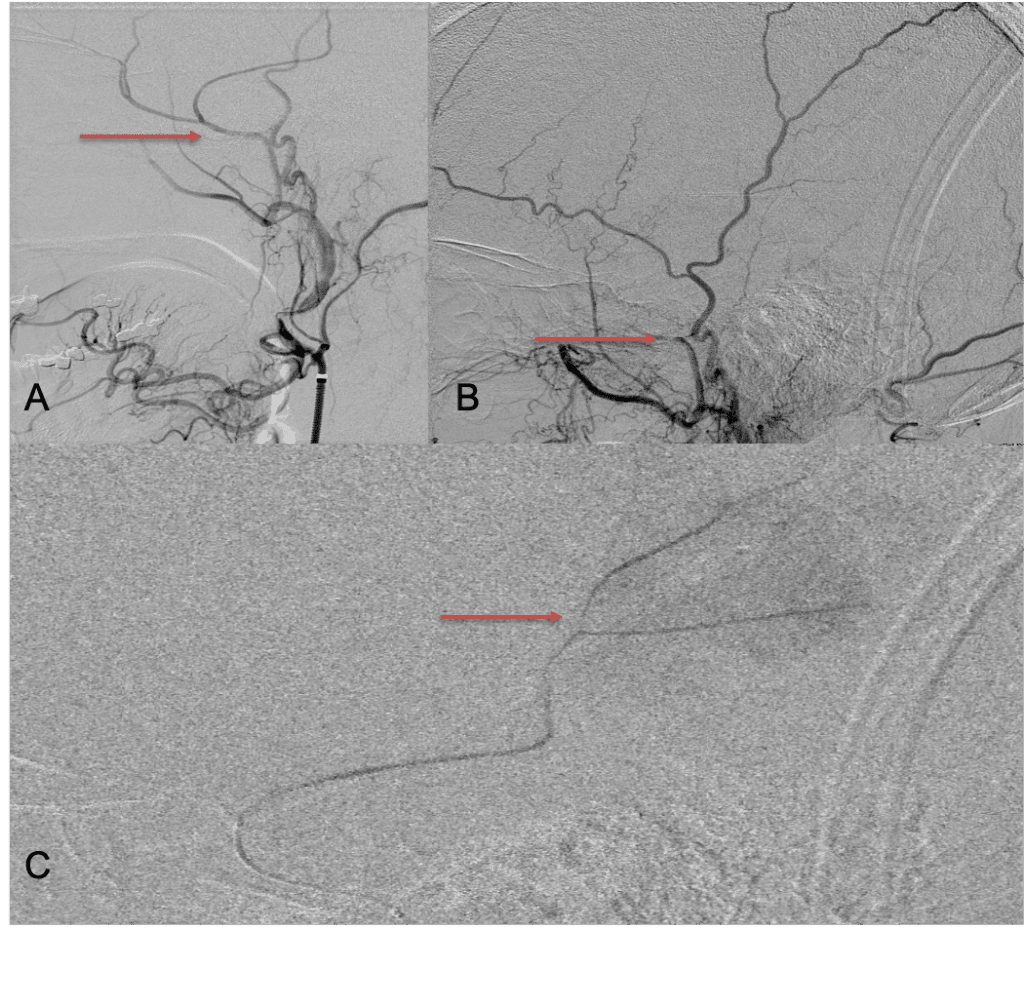

A woman in her 80s developed mild dizziness and headache following incidental trauma working in her garage one day. She presented several weeks later to the ER and was diagnosed with bilateral subdural hematomas, which were initially managed with observation, low dose Decadron, considering the mildness of symptoms, advanced age, and history of CLL with thrombocyptopenia (<100k). Over the next 4 weeks, the collections remained relatively stable with evidence of slight growth (10 to 12 mm thickness, and 2 mm right to left shift) on NCT (Figure 1. A and B).

Figure 1. A) 6 weeks post mild trauma B) 4 weeks post mild trauma demonstrates stable subacute subdural collections with mild growth and sulcal effacement.

CT follow-up at 1 week demonstrates early resorption. 2 weeks post MMA embolization, resolution of the left subdural collection with new small thin acute hemorrhage in an otherwise stable right subdural collection is observed (Figure 3. A and B).

Figure 3. A) 1 week post MMA embolization demonstrating decreasing thickness bilaterally B) 2 weeks post MMA demonstrates resolution on left, with small new acute component on right with overall decreased thickness.

Clinically, the patient improved over the few weeks with the occasional transient twinge of a headache, but resolution of dizziness. Follow-up CT at 10 weeks demonstrated complete resolution of the bilateral subdural hematomas with our patient completely asymptomatic and back to all of her activities of daily living. Considering her history of thrombocytopenia and CLL, we will continue to monitor her into the future and are excited about her progress and recovery. (Figure 4. A and B)

Figure 4. A and B) – 10 weeks following embolization demonstrates complete resolution of bilateral collections both acute and chronic.